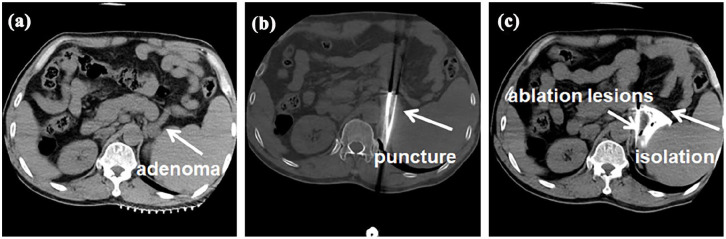

Aldosterone-producing adenomas and cortisol-secreting adenomas are among the most common functional tumors of the adrenal gland. Primary aldosteronism often leads to refractory hypertension and significantly increases the long-term risk of stroke and cardiovascular events. Autonomous cortisol-secreting adenomas are associated with various complications, including hypertension, hyperglycemia, osteoporosis, infections, and thrombosis. This report presented 2 cases of adrenal tumors: one case involving an aldosterone-producing adenoma and the other involving a cortisol-secreting adenoma. The endocrine functionality of these tumors was assessed using standardized endocrine function tests, including supine and standing aldosterone tests and dexamethasone suppression tests. Bilateral adrenal vein blood sampling (AVS) was performed to localize the lesion responsible for the conditions. Both patients underwent treatment with Kangbo knife cryoablation. No immediate adverse events, such as puncture site pain, hematoma, or pneumothorax, were observed following the procedure. The patient with cortisol-secreting adenoma developed a postoperative pulmonary infection and minor pulmonary thrombosis, which were successfully managed. Postoperatively, both patients achieved biochemical remission, with normalization of aldosterone and cortisol levels. Clinical symptoms, including hypertension, hypokalemia, and moon facies, were significantly improved. Currently, there are no published reports on the use of cryoablation for the treatment of adrenal cortisol-secreting adenomas. To our knowledge, this study presents the first documented cases of AVS-guided Kangbo knife cryoablation for the treatment of aldosterone-producing adenoma and autonomous cortisol-secreting adenoma. The favorable clinical and biochemical outcomes achieved in this study highlight the potential of Kangbo knife cryoablation as a safe and effective novel therapeutic approach for these functional adrenal tumors.